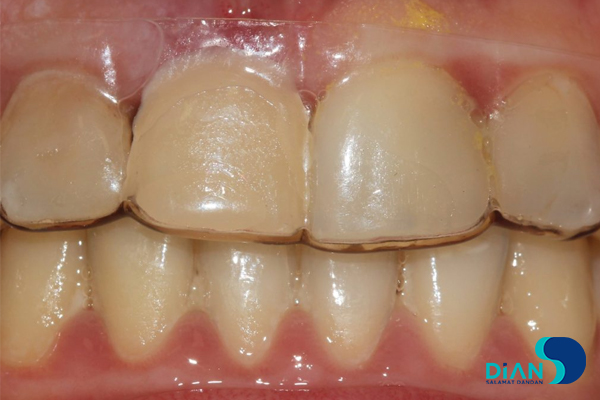

In order to hide defect in aesthetic zone the dentist made temporary cap, which will be used before implant integration.